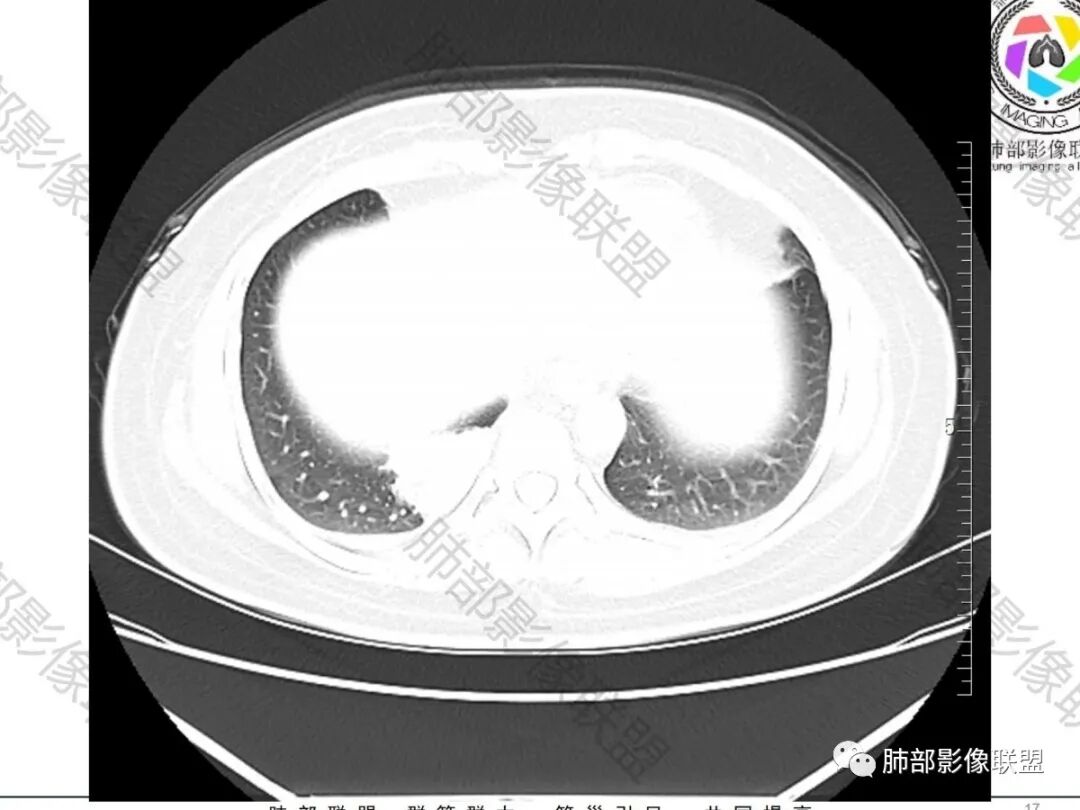

第一部分  病例资料

2.右肺下叶脊柱旁类椭圆形块影,边界清楚,密度偏低,隐约见轻度强化囊壁样结构,均匀一致,中央区域未见强化,因属囊样块影。前外缘处显示“壁外”小范围轻度强化软组织密度影,未见磨玻璃晕。

3.块影边缘见匍行血管影,未显示体循环供血。病灶与支气管关系未能显示或呈现。

病灶相邻胸膜轻度强化,未见壁层胸膜侵入或突破。

4.双肺门及纵隔未见增大淋巴结。

5.右侧胸腔少量积液。

综合分析:

1.肺部囊样结节影,壁较均匀一致,未见强化(壁轻度强化),常见者为支气管囊肿。内容物可为气体、低密度液体、高密度液体(如伴出血或感染等)。

2.囊样结节影如外形欠规则,观察到血管样结构穿行,囊壁不均匀增厚或呈现壁结节,结节外边界较清楚磨玻璃晕等,应想到恶性病变可能。

3.如灶周未见明显渗出,患者缺乏呼吸系统临床症状,不宜轻易冠以“感染”的诊断意见。

4.支气管囊肿伴曲霉菌寄生临床常见。

本例未出现曲霉菌感染或寄生的影像学特征,未做出相关判断在情理之中。

病理曲霉诊断出乎预料。